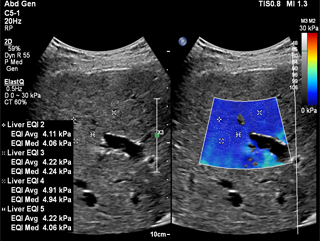

ElastQ imaging is a real-time, large Region of Interest (ROI), color-coded quantitative assessment of tissue stiffness. It is the only solution to offer both PureWave technology and high frame rate real-time shear wave imaging across abdominal applications. Clinicians can easily assess liver tissue stiffness using real-time feedback and make quantitative measurements with multiple sample points even retrospectively on DICOM stored images. Unique confidence map, used with the stiffness map, improve confidence of shear wave measurements. Both maps can be displayed side-by-side, which reduces workflow steps and allows for simultaneous map correlation during acquisition and measurement phases.